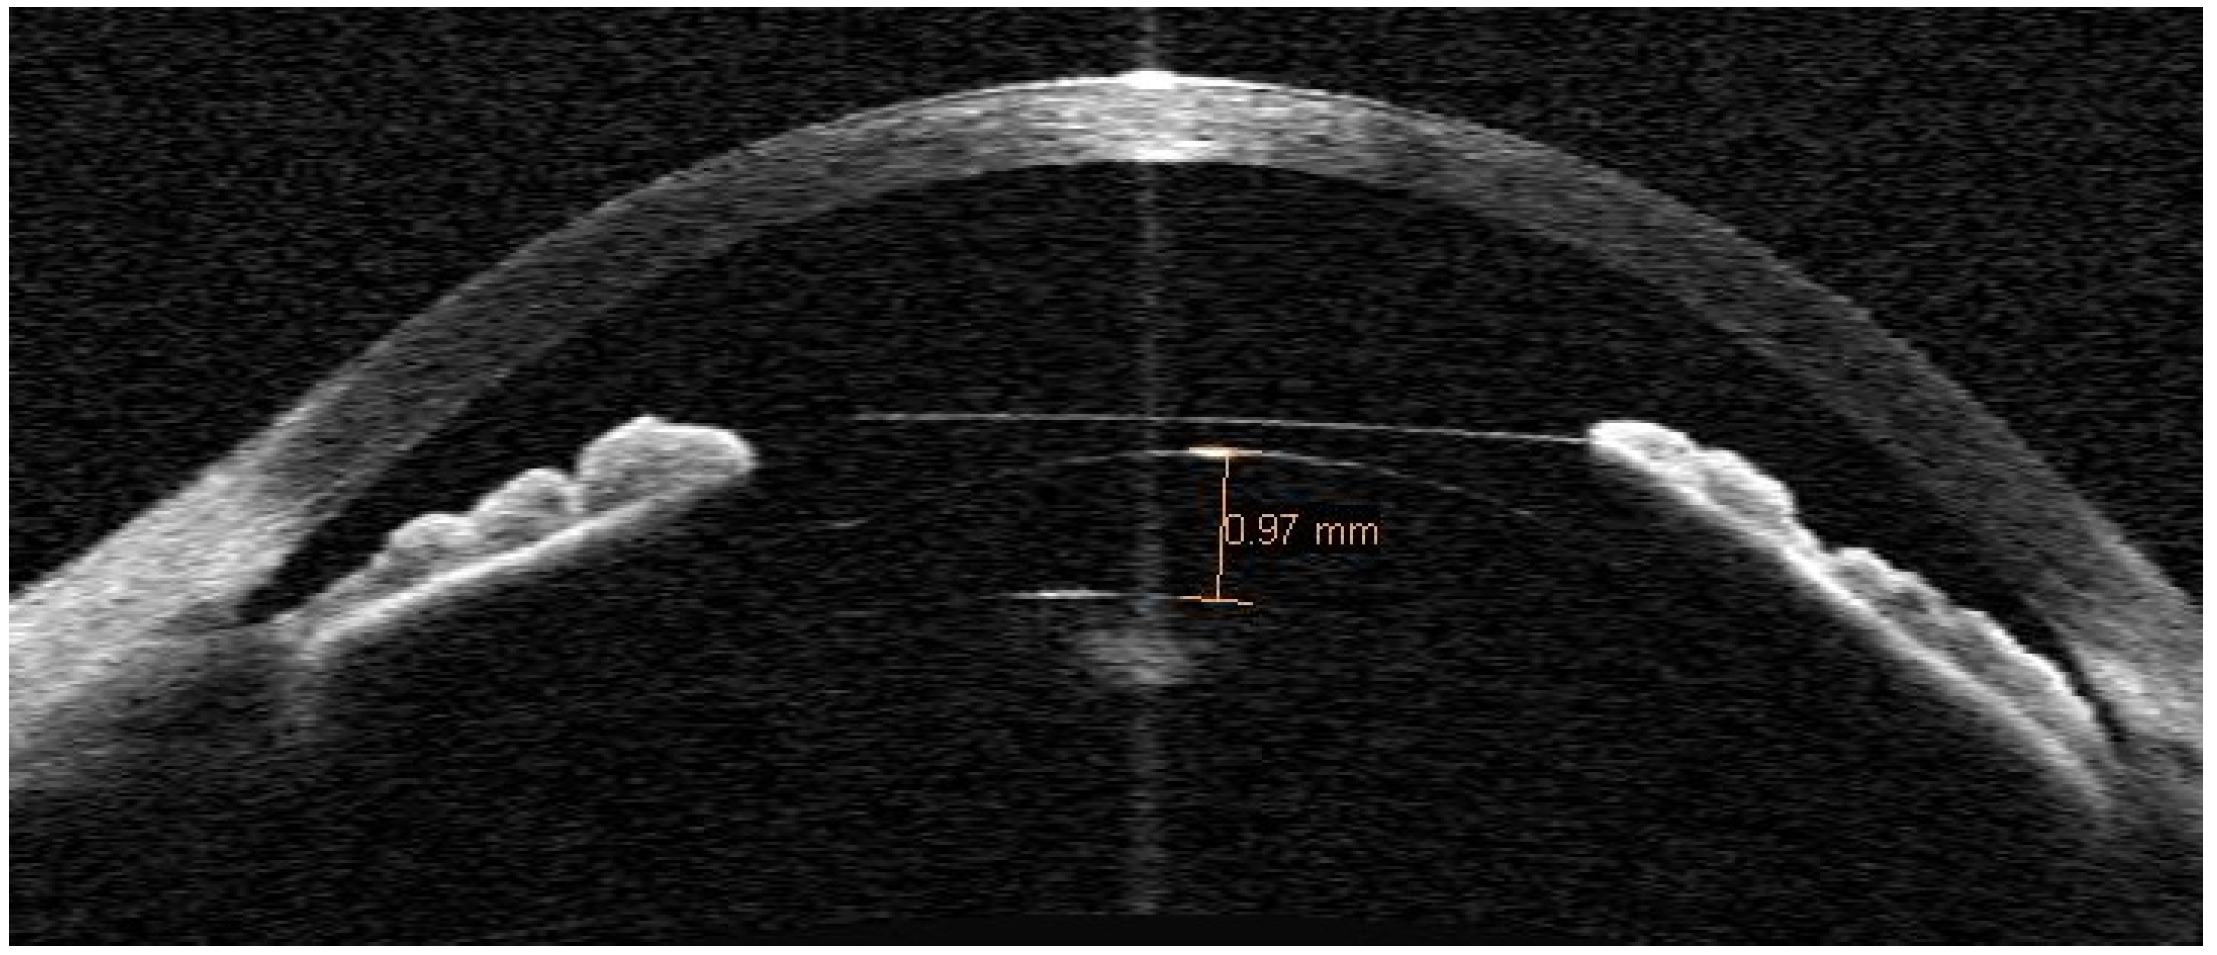

At three months postoperatively, the ICL position was assessed using anterior segment optical coherence tomography (AS-OCT) (Visante, Zeiss Meditec AG, Jena, Germany). The central vault was measured using the central vault line caliper by placing the line between the posterior ICL surface and the anterior crystalline lens surface apex (Figure 1). The AS-OCT imaging was performed under dim lighting conditions, with the patient fixating on the device’s in-built fixation target. Uncorrected distance VA was measured with the same VA chart as was used preoperatively and autorefraction was performed using the same autorefractor. The postoperative spherical-cylinder autorefraction was defined as postoperative manifest refraction.

Figure 1.

Anterior segment optical coherence tomography of an eye, implanted with a myopic ICL, exhibiting a 970 µm vault.